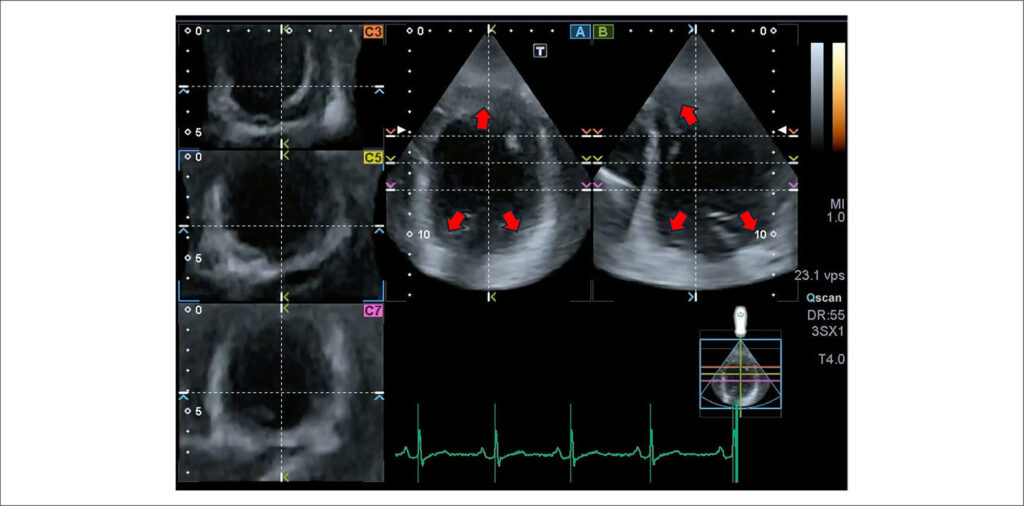

A análise do strain pela técnica de ST2D tem seu papel bem documentado e representa uma importante ferramenta complementar na avaliação da mecânica cardíaca, agregando valor na identificação de injúria miocárdica incipiente e subclínica em diferentes cenários clínicos. Um expressivo avanço relacionado à ecocardiografia foi o desenvolvimento do ST3D, que tem o potencial de superar muitas limitações intrínsecas à tecnologia bidimensional, oferecendo parâmetros adicionais de deformação miocárdica (como por exemplo a area strain) e uma quantificação mais abrangente da geometria e função do miocárdio ventricular esquerdo, a partir de uma única aquisição de imagem. Dentre as suas principais limitações, destacam-se a baixa resolução temporal e espacial, além da dependência de imagens de boa qualidade e do operador bem treinado. Embora seja uma técnica relativamente recente, ainda em desenvolvimento, vários estudos experimentais e algumas investigações clínicas já demonstraram a reprodutibilidade e a potencial aplicabilidade do ST3D. Este artigo tem o objetivo de agregar informações para uma adequada análise do strain tridimensional do ventrículo esquerdo e explorar os seus principais pontos de vulnerabilidade, discutindo variáveis importantes para aumentar a acurácia e a reprodutibilidade desta tecnologia.